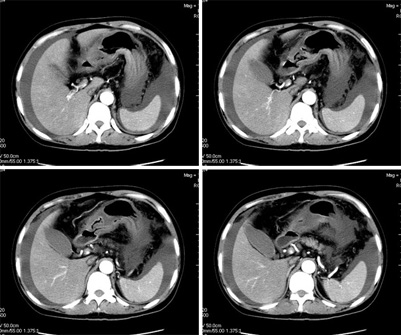

增强

真是少见!至少本人从未见过!整个消化道除了胃壁以外整套小肠及结肠肠壁均不同程度增厚水肿,肠壁间未见积气,亦未见明显的血运障碍(肠细膜上动静脉均显示很好)。盆腹腔积液。

真是少见!至少本人从未见过!整个消化道除了胃壁以外整套小肠及结肠肠壁均不同程度增厚水肿,增强明显分层[粘膜层及浆膜层明显强化,粘膜下层强化轻]。结合病史考虑肠道缺血改变[病因待查--血管炎,结缔组织疾病等]

楼主上传图像很漂亮。把每幅图像放大,增强扫描,发现肠系膜上静脉管腔变形,其内见半圆形等密度影,结合病史,考虑肠系膜上静脉栓塞并肠壁间水肿,腹水。(这是首次发的话题)

我们仔细看了三期增强的动静脉血管,未看见血栓的形成,因为三期的片子太多有168张,无法全部上传,在动脉期及静脉期看到下腔静脉及门静脉内密度不均匀在平衡期均显示均匀,所以不考虑血栓形成引起的回流障碍.刚才老公在电脑边走过(他是外行),发表意见说这人是不是吃了什么东西引起肠子中毒.我想了一下似乎有道理,但是是什么东西会引起这样的改变,并且从病程上来看有一个多月的病史,又不是急性发作,网上高手们给予指点,如需要更多的另两期的图片,我将上传.

肝周、脾脏周围可见腹水,盆腔可见积液;肠管壁广泛的增厚,密度减低,可见液体积聚在粘膜下层里面,首先还是考虑血管引起的。感染放在后面吧。

肠管壁增厚,以升结肠、横结肠明显,肠袋变浅,cta显示肠系膜上动、静脉显影清楚,管腔未见狭窄,同时大量腹水,考虑:肠麻痹水肿?食物中毒?

本例ct表现是肠道的整体性充血、水肿,以结肠特别是横结肠、升结肠、盲肠为显著,横结肠一眼粗略看过去,极似极度水肿之胰腺。回肠末段亦呈明显近似结肠改变,小肠则以充血为主,水肿相对轻微。诸段肠管无明显如溃疡、出血等局部损害,重度腹水。肝脏体积变小,肝裂增宽,以肝圆韧带为明显。肝脏各部比例尚正常,无局部外突或内凹,密度均匀一致。胆囊增大,所给图片及楼主已经仔细观察过,肝段下腔静脉肠系膜静脉均正常。